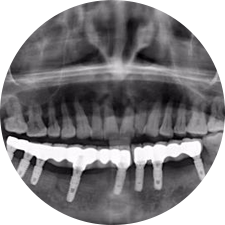

口腔種植是將人工牙根通過手術(shù)植入牙骨內(nèi),獲得牙槽骨牢固的支持,通過特殊的裝置和方式連接牙修復(fù)體,獲得與天然牙功能、結(jié)構(gòu)以及美觀相似的效果。

河北惟德口腔醫(yī)院擁有國(guó)內(nèi)豐富的半口/全口、即刻負(fù)重種植案例,十八年案例跟蹤分析,總結(jié)梳理出的各種不同類型的種植案例,Nobel種植體系針對(duì)半口/全口缺牙患者,通過4-8顆種植體可快速達(dá)到牙齒重建,不僅植入種植體較少,節(jié)省費(fèi)用,手術(shù)時(shí)間更短。

術(shù)前患者CBCT口掃1:1三維重建,模擬手術(shù)過程及預(yù)測(cè)術(shù)后治療效果,確定每顆植體植入的適合的種植位點(diǎn)、深度及角度,有效避免損傷頜骨重要解剖結(jié)構(gòu),提高手術(shù)準(zhǔn)確度與安全性。

Noble口腔種植體系基本不受年齡限制,適用于缺牙修復(fù),也適用于牙槽骨萎縮、骨質(zhì)疏松、高血壓、糖尿病、超高齡的患者,即種即用,只需少量微小種植體,便可輕松微痛快速重建全口咬合,特殊力學(xué)設(shè)計(jì),針對(duì)許多年紀(jì)較大,骨質(zhì)條件差,身體耐受力差的缺牙老人也能完成“即種即用”,受到廣泛好評(píng)。

惟德口腔種植體系是以患者感受為中心,取代傳統(tǒng)種植牙手術(shù)需要翻瓣、打孔、縫合,術(shù)前、術(shù)中、術(shù)后的繁復(fù)流程,采用3D導(dǎo)航微創(chuàng)準(zhǔn)確種植技術(shù),通過數(shù)字化CAD/CAM掃描技術(shù)獲得缺牙患者口腔數(shù)據(jù),以數(shù)據(jù)為基礎(chǔ)重建口腔模型進(jìn)行模擬種植。

術(shù)前將患者口內(nèi)的CBCT數(shù)據(jù)及咬合關(guān)系上傳到計(jì)算機(jī)中,建立1:1三維重建,模擬手術(shù)過程及預(yù)測(cè)術(shù)后治療效果,找出較佳種植位點(diǎn)、深度及角度,獲取實(shí)際種植體在頜骨內(nèi)的具體三維位置,有效避免損傷頜骨重要解剖結(jié)構(gòu),大大降低手術(shù)風(fēng)險(xiǎn),提升種植成功率。